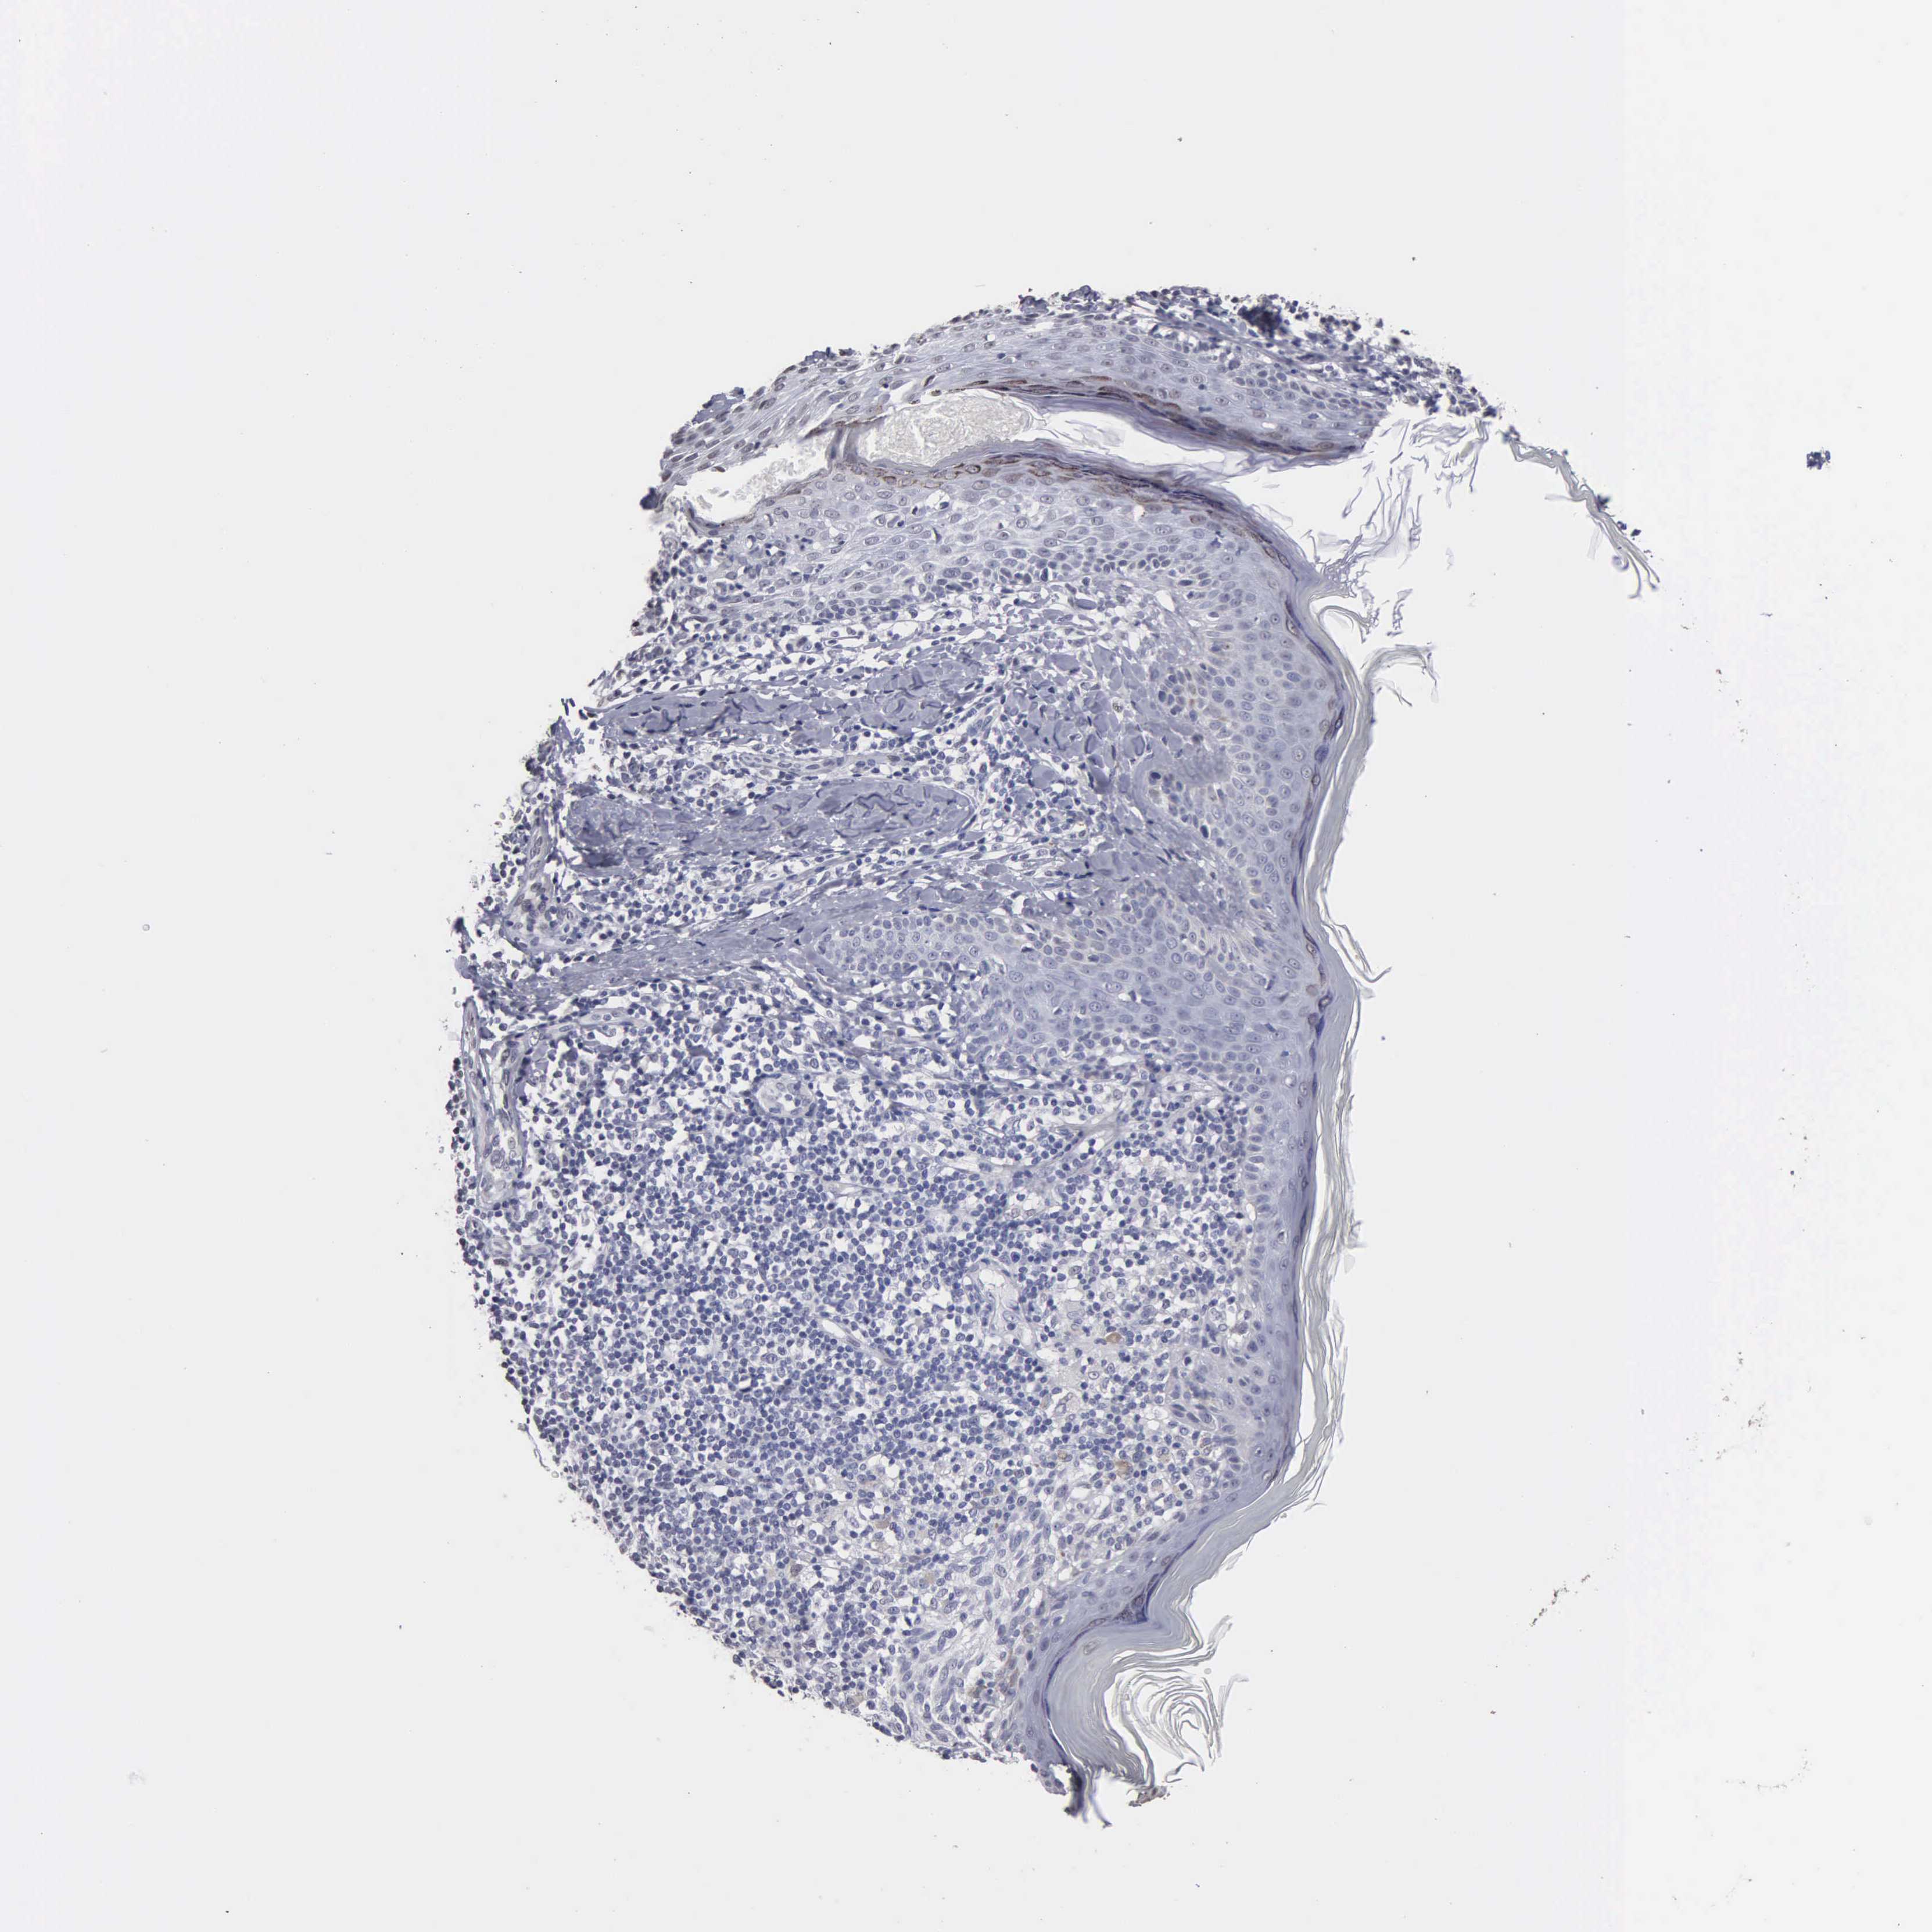

Antibody HPA000728

Antibody HPA076321

MELANOMA - Protein expressioni

A mouse-over function shows sample information and annotation data. Click on an image to view it in a full screen mode. Samples can be filtered based on level of antibody staining by selecting one or several of the following categories: high, medium, low and not detected. The assay and annotation is described here.

Antibody staining in the annotated cell types in the current human tissue is reported as not detected, low, medium, or high, based on conventional immunohistochemistry profiling in selected tissues. This score is based on the combination of the staining intensity and fraction of stained cells.

Each image is clickable and will lead to virtual microscopy that enables deeper exploration of all samples and also displays staining intensity scores, fraction scores and subcellular localization as well as patient and tissue information for each sample.

Malignant melanoma, NOS

Malignant melanoma, Metastatic site